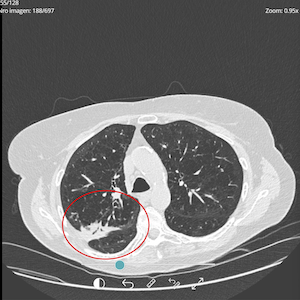

PRE-TREATMENT

OCTOBER 2024

POST-TREATMENT

SEPTEMBER 2025